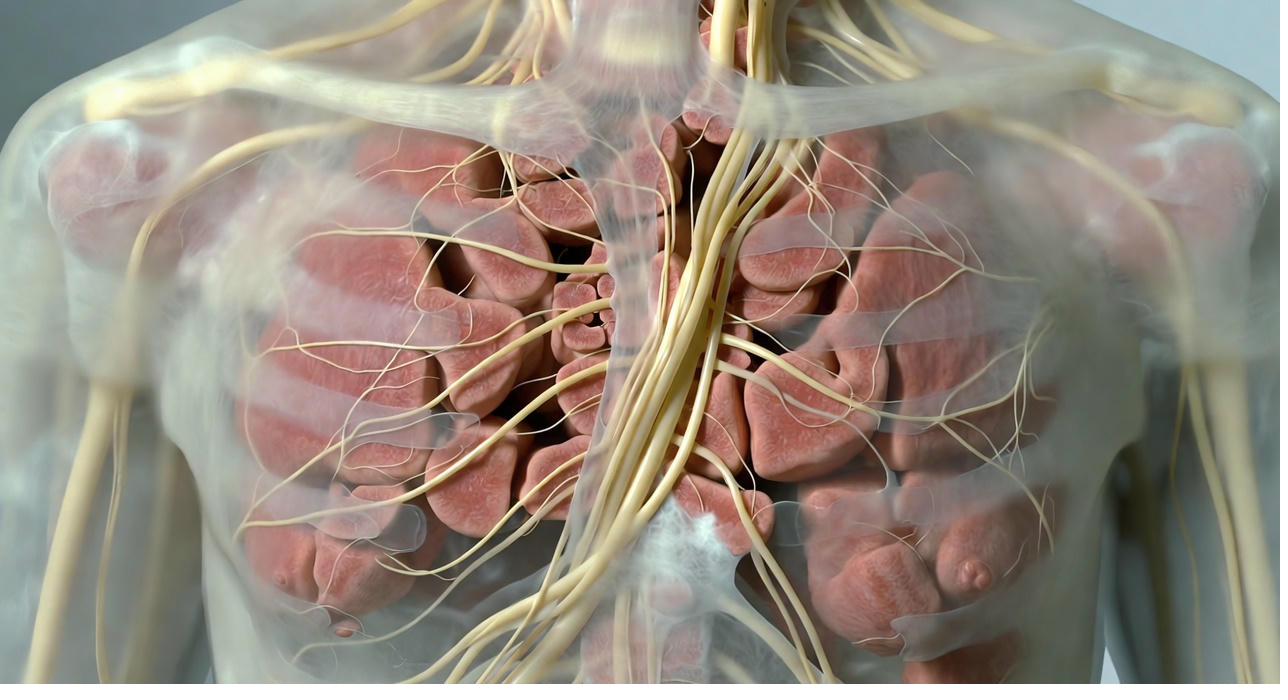

Your nervous system is designed with two opposing modes. Fight-or-flight, the sympathetic branch, prepares you for action: heart racing, muscles tensing, senses sharpening to face a threat.

The opposite mode, rest-digest-heal, driven by the parasympathetic branch, allows recovery: slowing the heart, relaxing tissues, repairing damage.

These modes should balance beautifully, switching as needed. Threats can be from childhood trauma or current life stresses. Some things are in the past and some remain, but the effect on the body can be long-lasting.

In the State of Fibromyalgia, something shifts. Fight-or-flight becomes chronically dominant, running at a low but constant level, even when no danger is present.

This isn't weakness or "anxiety." It's a biological response to ongoing signals of threat from the body. And the biggest source of those signals? Restricted Fascia.

Tight, adhesive Fascia sends constant "danger" messages through compressed nerves and tense tissues. The brain interprets this as a threat, keeping sympathetic drive high. Hormones like adrenaline and noradrenaline stay elevated, muscles and Fascia tighten further, sleep fragments, and every sensation gets amplified.

Recent research shows this sympathetic overactivity isn't just a side effect. It's actively sustaining Myofascial pathology. Tight Fascia feeds sympathetic drive, which tightens Fascia more, creating an immune-mediated inflammation loop that locks the pain in place.

When we release Fascia, the threat signals quiet. Fight-or-flight naturally drops, breaking the loop and allowing the body to finally rest.